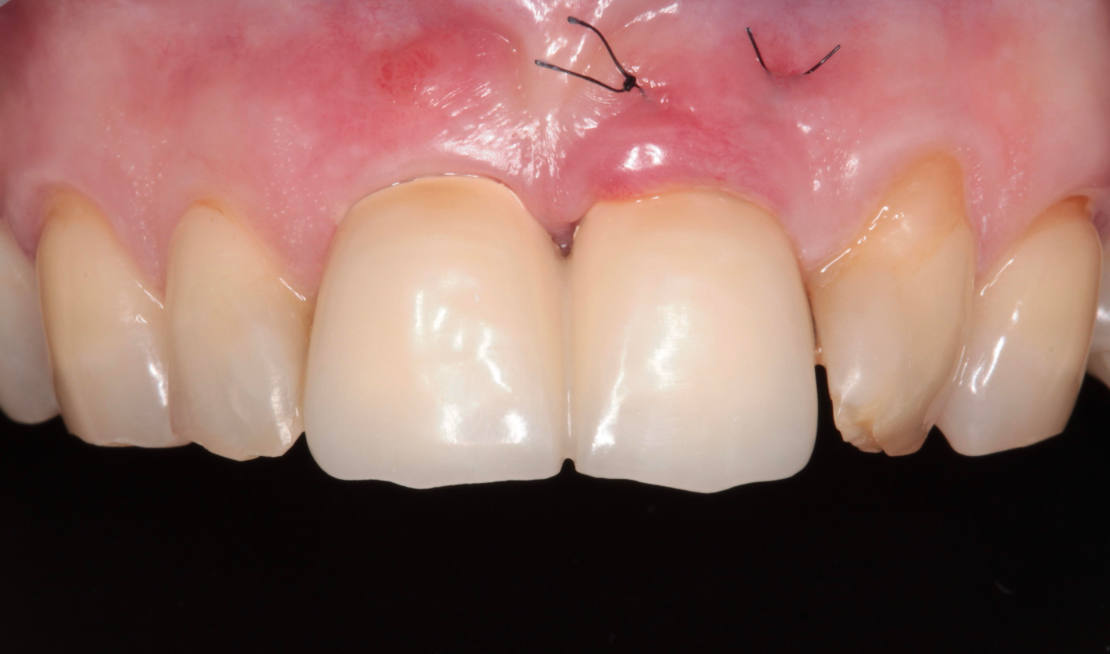

45-ročná pacientka sa obrátila na našu kliniku s bolesťou v oblasti horných stredných rezákov (obr. 1). Pri dôkladnom vyšetrení a CT diagnostike bola v oblasti zuba č. 11 zistená vertikálna fraktúra koreňa (obr. 2). V oblasti zuba č. 21 palatinálne bol prítomný hlboký kaz koreňa (obr. 3).

Vďaka týmto postupom bola operácia veľmi rýchla a pacientka odišla z ordinácie plne rehabilitovaná. Minimálne invazívnym spôsobom boli extrahované horné jednotky (obr. 6).